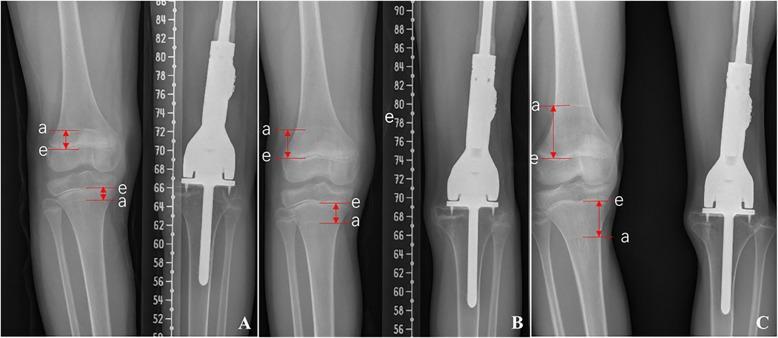

Forty-five children with bone sarcoma around the knee, who underwent custom-made extendible endoprosthesis replacements, were included in this study. The average follow-up was 10.1 years. Survival, prosthetic-related complications and revision, functional outcomes, and influence on growth by prosthesis implantation were recorded.

The 5-year disease-free survival and overall survival are 54.9% and 72.7%, and the 5-year prosthesis survival rate is 59.4%. The prosthesis was extended 4.2 cm in average. Limb length discrepancies of 20 patients were within 2 cm, and growth inhibition of proximal tibial epiphysis by passive implant insertion was observed. Aseptic loosening in 7 patients was the most significant complication. The Musculoskeletal Tumor Society score at last visit was 83.2%.